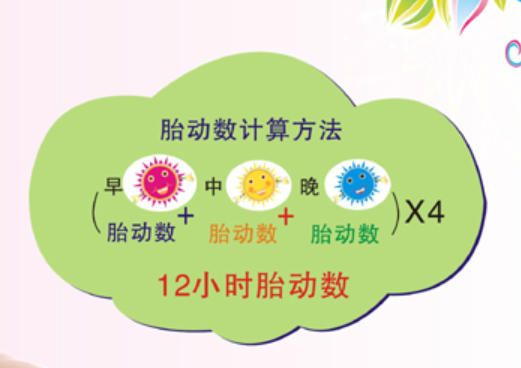

可以在三餐后,记录1小时内胎动的次数

踢一下停下来计1次,连续动多次也计1次

每次胎动必须要有一定的间隔才算第二次

正常胎动1小时不少于3-5次,

12小时30-40次以上,